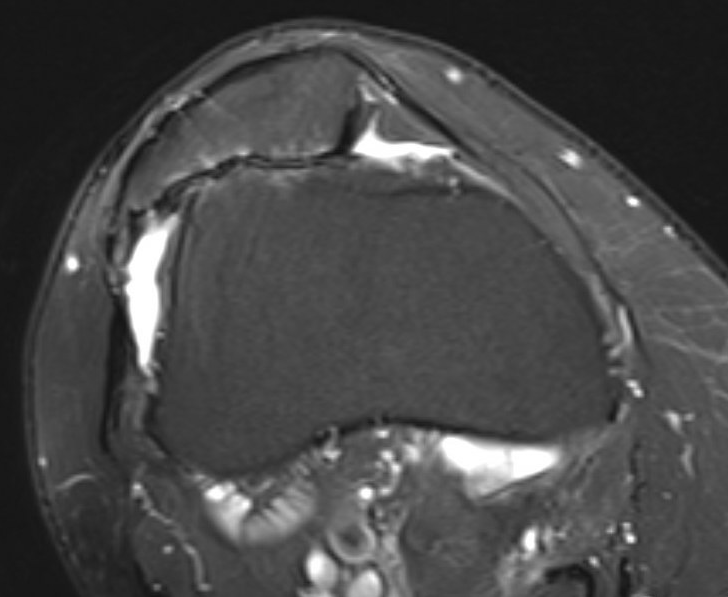

MRI

Severe lateral PFJ OA in the setting of maltracking / subluxation / tilt